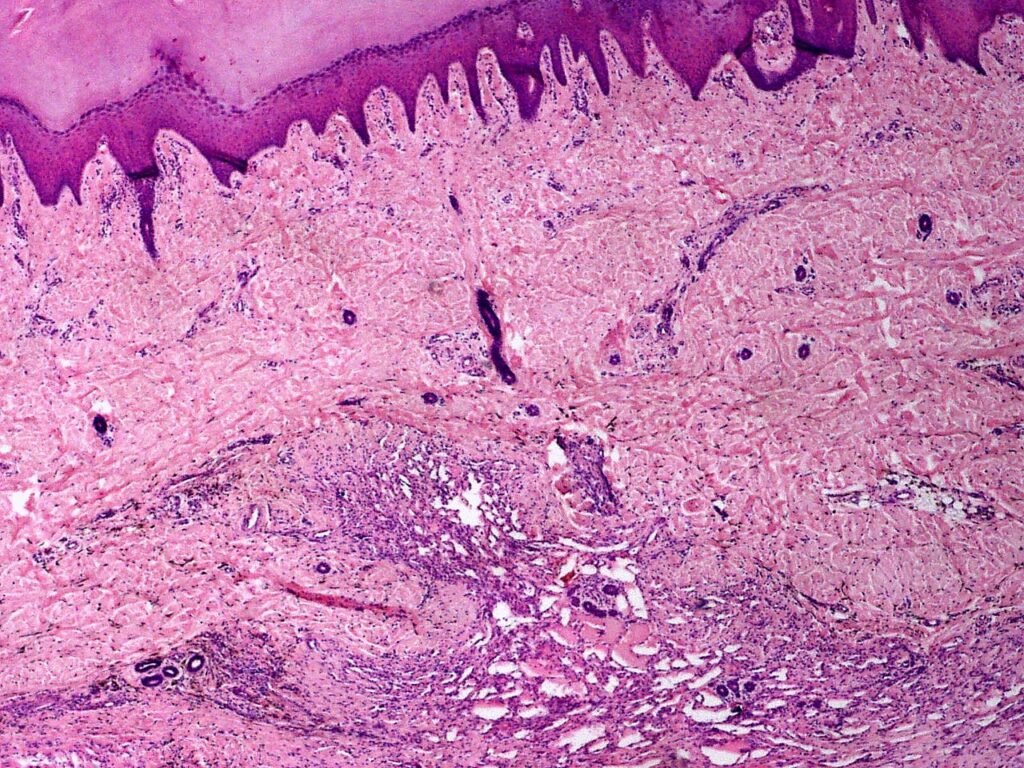

Biopsja skóry

>>>Biopsja skóry to badanie diagnozujące także w innych stanach chorobowych, jak np.: pęcherzyca, choroba Menkesa.

Histopatologia

Histopatologia to dziedzina medycyny zajmująca się badaniem tkanek i komórek w celu diagnozowania chorób. W ramach tego badania, próbki tkankowe są pobierane z organizmu pacjenta, a następnie poddawane analizie mikroskopowej. Histopatolodzy oceniają zmiany morfologiczne w komórkach, co pozwala na identyfikację różnych schorzeń, w tym nowotworów, stanów zapalnych oraz innych patologii. Badania histopatologiczne są kluczowe w procesie diagnostycznym, ponieważ dostarczają informacji o charakterze i stopniu zaawansowania choroby. Analiza tkanek umożliwia także określenie odpowiednich metod leczenia. Histopatologia odgrywa istotną rolę w medycynie, gdyż pozwala na wczesne wykrycie wielu schorzeń, co zwiększa szanse na skuteczne leczenie. >>>

Histopatologia to badanie diagnozujące także w innych stanach chorobowych, jak np.: pęcherzyca, protoporfiria erytropoetyczna, glejak wielopostaciowy, histoplazmoza, sporotrychoza, Żółta gorączka, choroba Creutzfeldta-Jakoba.